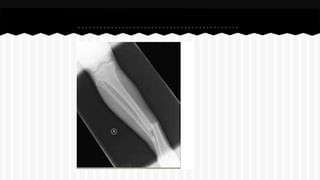

RESPONDA O NOME DO OSSO EM QUE

SE ENCONTRA A (S) FRATURA (A).